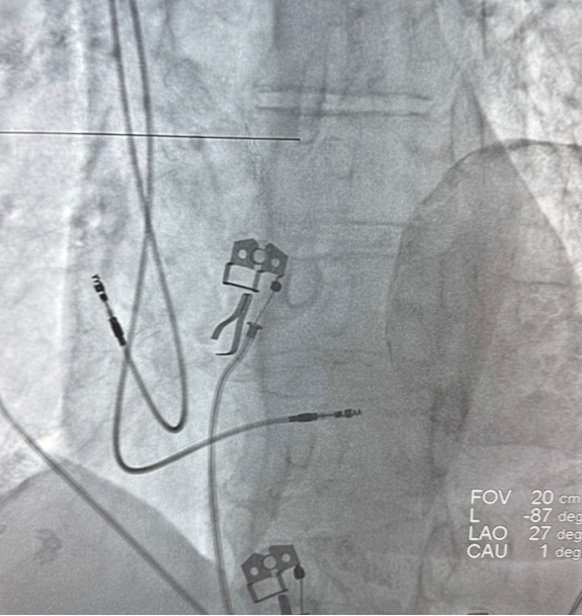

La forma más común de realizar este cierre es mediante un procedimiento mínimamente invasivo:

Se realiza bajo anestesia general.

Se hace una pequeña punción (similar a un cateterismo) en una vena de la ingle (pierna).

Se introduce un catéter a través de la vena hasta llegar al corazón y la Orejuela Izquierda. A través del catéter, se despliega un dispositivo de cierre (que parece un pequeño paraguas o tapón) dentro de la Orejuela. Este dispositivo sella permanentemente la abertura de la Orejuela.

- Reducción del Riesgo de ACV: Proporciona una protección contra el ACV similar a la de los anticoagulantes.

- Evita Anticoagulantes: Permite a los pacientes de alto riesgo dejar de tomar medicamentos anticoagulantes orales a largo plazo.